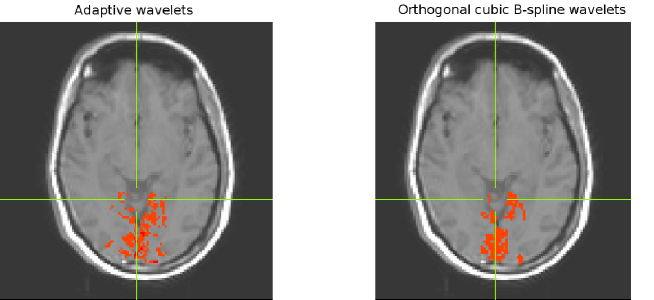

We tested the proposed method with data obtained from a visual stimulation experiment, with 16 slices of voxels, the size of which is 1.8 mm 1.8 mm 5 mm. We performed segmentation with the SPM software package, and generated the adaptive wavelets using the domain corresponding to the gray-matter layer. The thresholded binary domain is shown in Figure 4.10. Using the standard orthogonal wavelets, the analysis resulted in 1032 detected voxels, with the adapted wavelets it resulted in 1214 active voxels. In both cases the sensitivity parameter is taken to be 0.001. This suggests an improved sensitivity, with a detection of larger number of voxels, as shown in Figure 4.11.